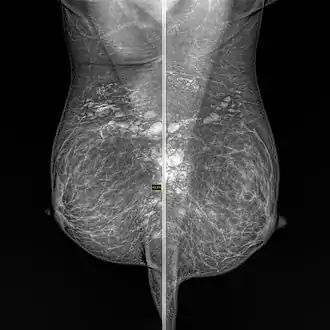

- Lymph node: Granulomatous lymphadenitis[3][4]

- Breast: Granulomatous mastitis[9][10]